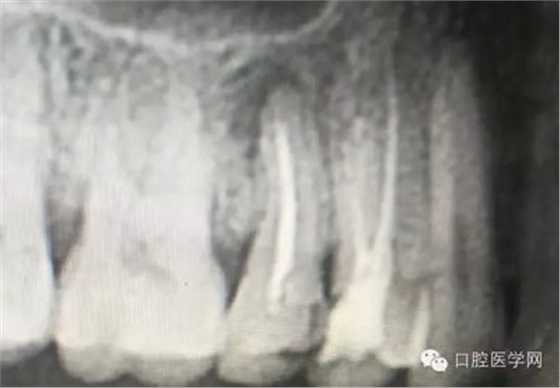

根管再治療是我們比較頭疼的,尤其是那些冠修復(fù)過的,我們有很多的麻煩需要去溝通,比如可能導(dǎo)致的側(cè)穿、可能沒有看到的腐質(zhì)、可能導(dǎo)致的崩瓷,或者是后期可能出現(xiàn)冠折......這些需要我們和患者好好的溝通。全瓷冠還好些,金屬冠根測(cè)的時(shí)候很是麻煩,總之我們做修復(fù)的時(shí)候不要單純的追求速度,追求效益,適當(dāng)?shù)淖⒁庀挛覀兊幕A(chǔ)治療和設(shè)計(jì)。